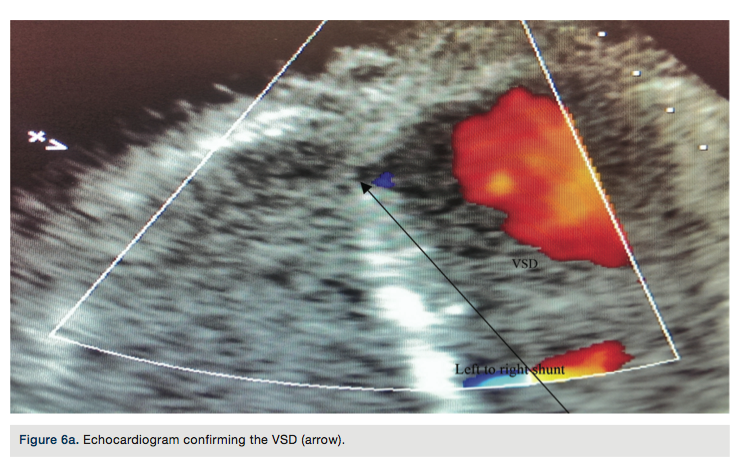

branch had a 60 to 70% stenosis at its ostium. The second obtuse marginal off the left circumflex artery revealed an 80% stenosis (Figure 2). Next, a 6 Fr femoral right (FR) 4 diagnostic catheter (Boston Scientific) catheter was advanced over the guide wire. The right coronary artery (RCA) was cannulated and contrast was injected to visualize the artery. Angiograms revealed a 50% stenosis in the mid portion (Figure 3). The posterior descending artery (PDA) was free of disease.